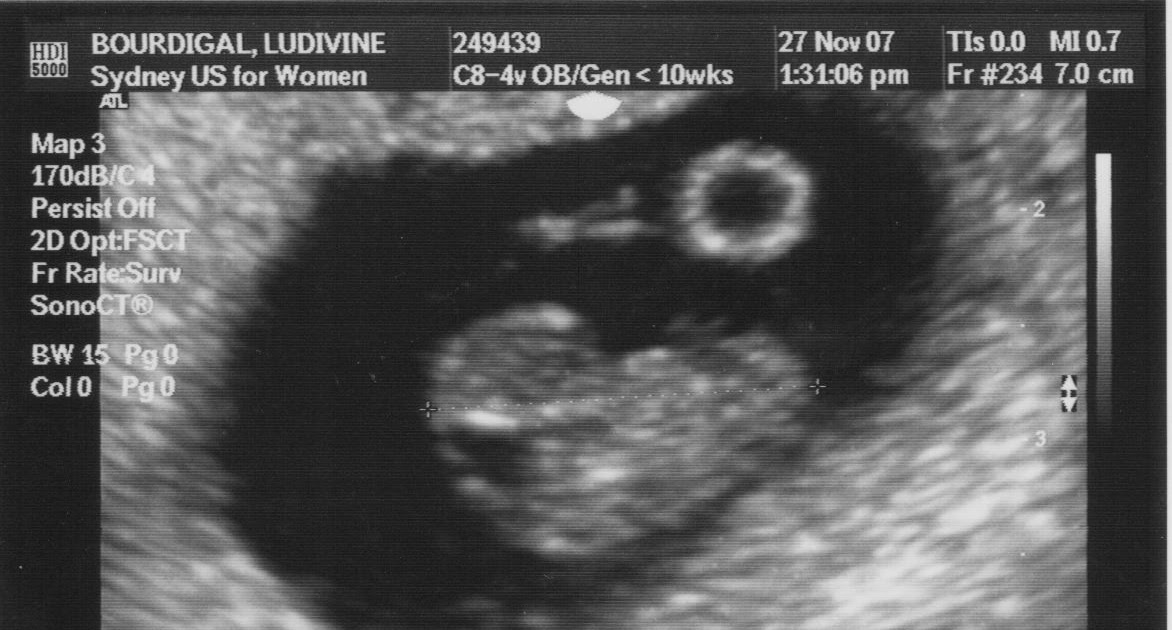

L'examen est moins spectaculaire parce que le fœtus est plus gros et qu'il n'est possible de le voir que par petites parties Une échographie de grossesse de 6 semaines est essentielle pour déterminer avec précision si vous êtes enceinte et si des anomalies sont présentes. L'échographie à 6 semaines de grossesse est une étape clé pour les futurs parents, car elle permet de confirmer la viabilité de la grossesse et d'entendre pour la première fois les battements cardiaques du bébé

Echographie 6 Semaines Grossesse. Echographie de grossesse quand et pourquoi Préparation pour l'échographie et déroulement de l'examen Avant‍ de réaliser une échographie 6 semaines de grossesse, il est important de se préparer‌ correctement À 8 semaines L'embryon mesure environ 5 millimètres (longueur céphalo-caudale)

6e semaine de grossesse symptômes, développement du bébé et. À 8 semaines L'embryon mesure environ 5 millimètres (longueur céphalo-caudale) Quelques jours après la nidation, l'œuf devient rapidement un embryon